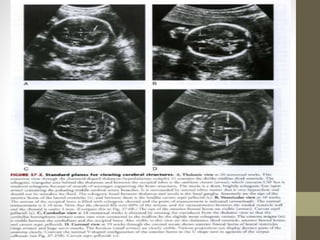

What to see? IN SKULL

โ€ข 4.MIDLINE STRUCTURES(T-THALAMIC)-----CSP

โ€ข 5.VENTRICLES(T-VENTRICULAR)

โ€ข 6.POSTERIOR FOSSA(CEREBELLAR PLANE)